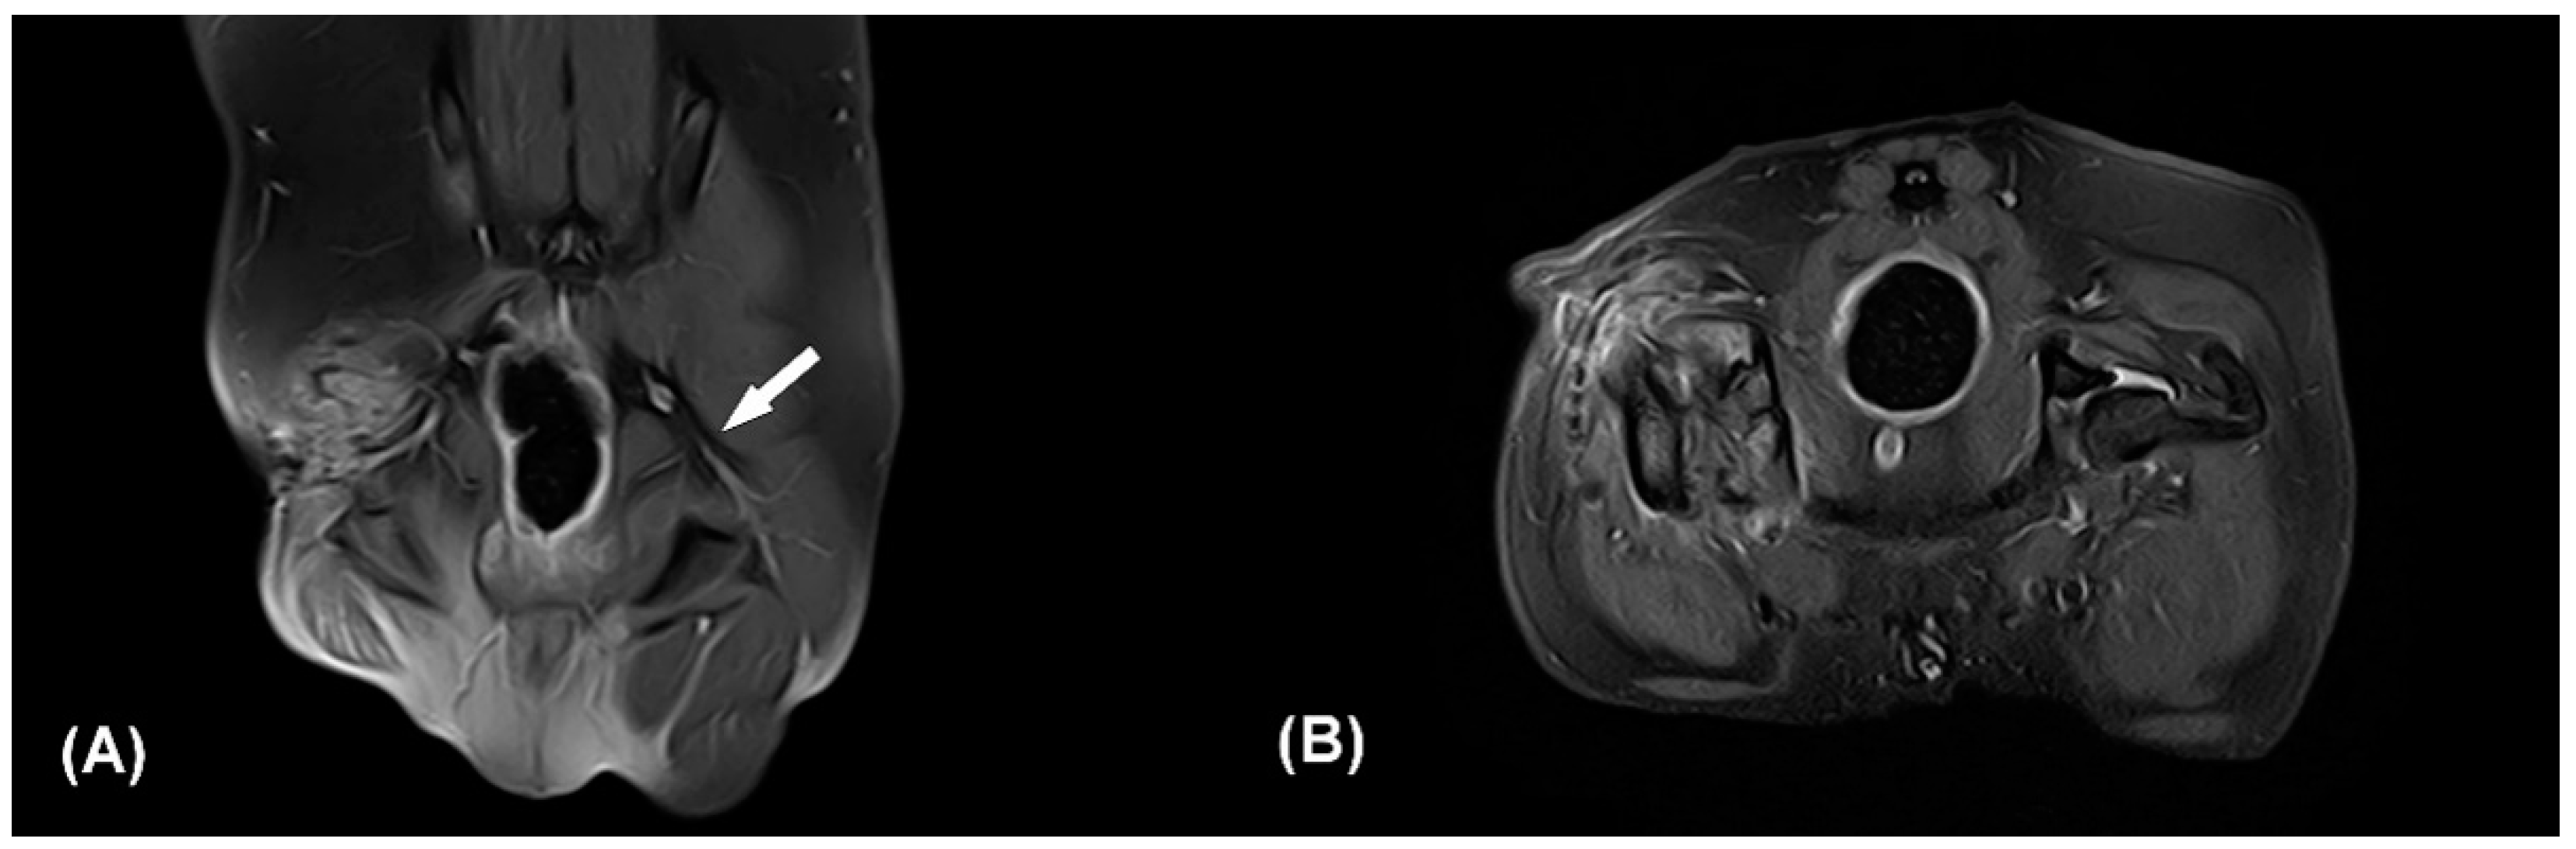

Figure 2. Contrast enhanced fat-suppressed proton density weight images (CE-FS-PDWI) of dorsal (A) and transverse plane (B). The white arrow indicates the intact left sciatic nerve (A). The right sciatic nerve strand is not clearly identifiable (A,B). Note that focal discontinuity of the sciatic nerve, muscle fibrosis, and edema of surrounding soft tissue. Q: quadriceps muscle, Bi: biceps femoris muscle.

Based on the patient’s clinical signs, history, and the results of physical and neurological examinations, iatrogenic right-sided sciatic neuropathy was suspected since the neurological deficit was shown immediately after the previous operation and the skin incision was caudal to the greater trochanter where the sciatic nerve was located. The patient was sedated with intramuscular administration of medetomidine (30 μg/kg). Radiographic examination including ventrodorsal hip extended and lateral view of the pelvis and craniocaudal and open-leg mediolateral view was performed for the right coxofemoral joint. Despite of previous FHNO surgery, irregular bony proliferations around the osteotomy line and acetabular rim were identified on radiographs. Magnetic resonance imaging performed under general anesthesia revealed inconspicuous continuity of the right sciatic nerve at the greater trochanter level (Figure 2). In the transverse and dorsal planes, hypointense structures appearing as osteophytes were observed in the right greater and lesser trochanters and acetabulum on T1 and T2-weighted (W) and contrast enhanced fat-suppressed proton density weight images (CE-FS-PDWI). On T1W and T2W images, peripheral muscles were observed to be non-uniform in intensity due to fibrotic changes. Volumes of the right adductor, gluteal, quadriceps, biceps femoris, semitendinosus, and semimembranosus muscles were decreased compared with the left side, and fatty infiltration was present. These findings were consistent with sciatic nerve injury and muscle atrophy.